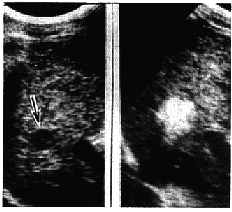

摘 要 目的:探讨超声介入注射无水酒精治疗肝癌的量化方法。方法:对86例162个复发性肝癌结节在超声引导下行无水酒精注射治疗(PEI),计算①酒精注射量与弥散范围最大径的相关系数;②肿块大小与酒精注射量的回归方程。结果:酒精注射量与弥散范围呈非常显著正相关(r=0.884,P=0.000), 肿瘤结节大小与酒精注射量的回归方程为:当肿瘤直径≤5cm时为Y=2.885X,当肿瘤直径>5cm时, 其回归方程为Y=1.805X(式中X为肿瘤最大径cm, Y为酒精注射量ml)。结论:通过酒精注射量与弥散范围的相关关系研究导出的肿瘤结节直径与酒精注射量的回归方程经临床应用与随访观察,具有肯定的疗效, 可作为行PEI时酒精注射量的计算方法。

ABSTRACT Objective:To probe the methodof percutaneous ethanol injection(PEI) in treatment of hepatocarcinoma. Methods:Onehundred sixty two recurrent hepatocarcinoma in 86 patients were treated by ultrasoundguided PEI. The interrelated coefficient of the quantity of alcohol injected into themasses and the diameters of spreading areaes of the alcohol on the screen were measured.Also the regressie equation of the diameters of the mass and the quantity of alcohol wascalculated. Results:The quantity of alcohol and the alcohol spreading area is markedlypositive interrelated (r=0.884, P=0.000). The regressive equation of the diameter of themass and the quantity of alcohol is Y=2.885X when the diameter of the mass is≤5cm, andY=1.805X when the mass is>5cm (X is the mass diameter, Y is the alcohol quantity. Theunit is ml). Conclusion:Hepatocarcinoma is cured by PEI with the quantified alcoholcalculated by the regressive equation of the diameter of the mass and the quantifiedalcohol inferred from the interrelationship between the quantity of alcohol and thediameter of spreading area of the alcohol.